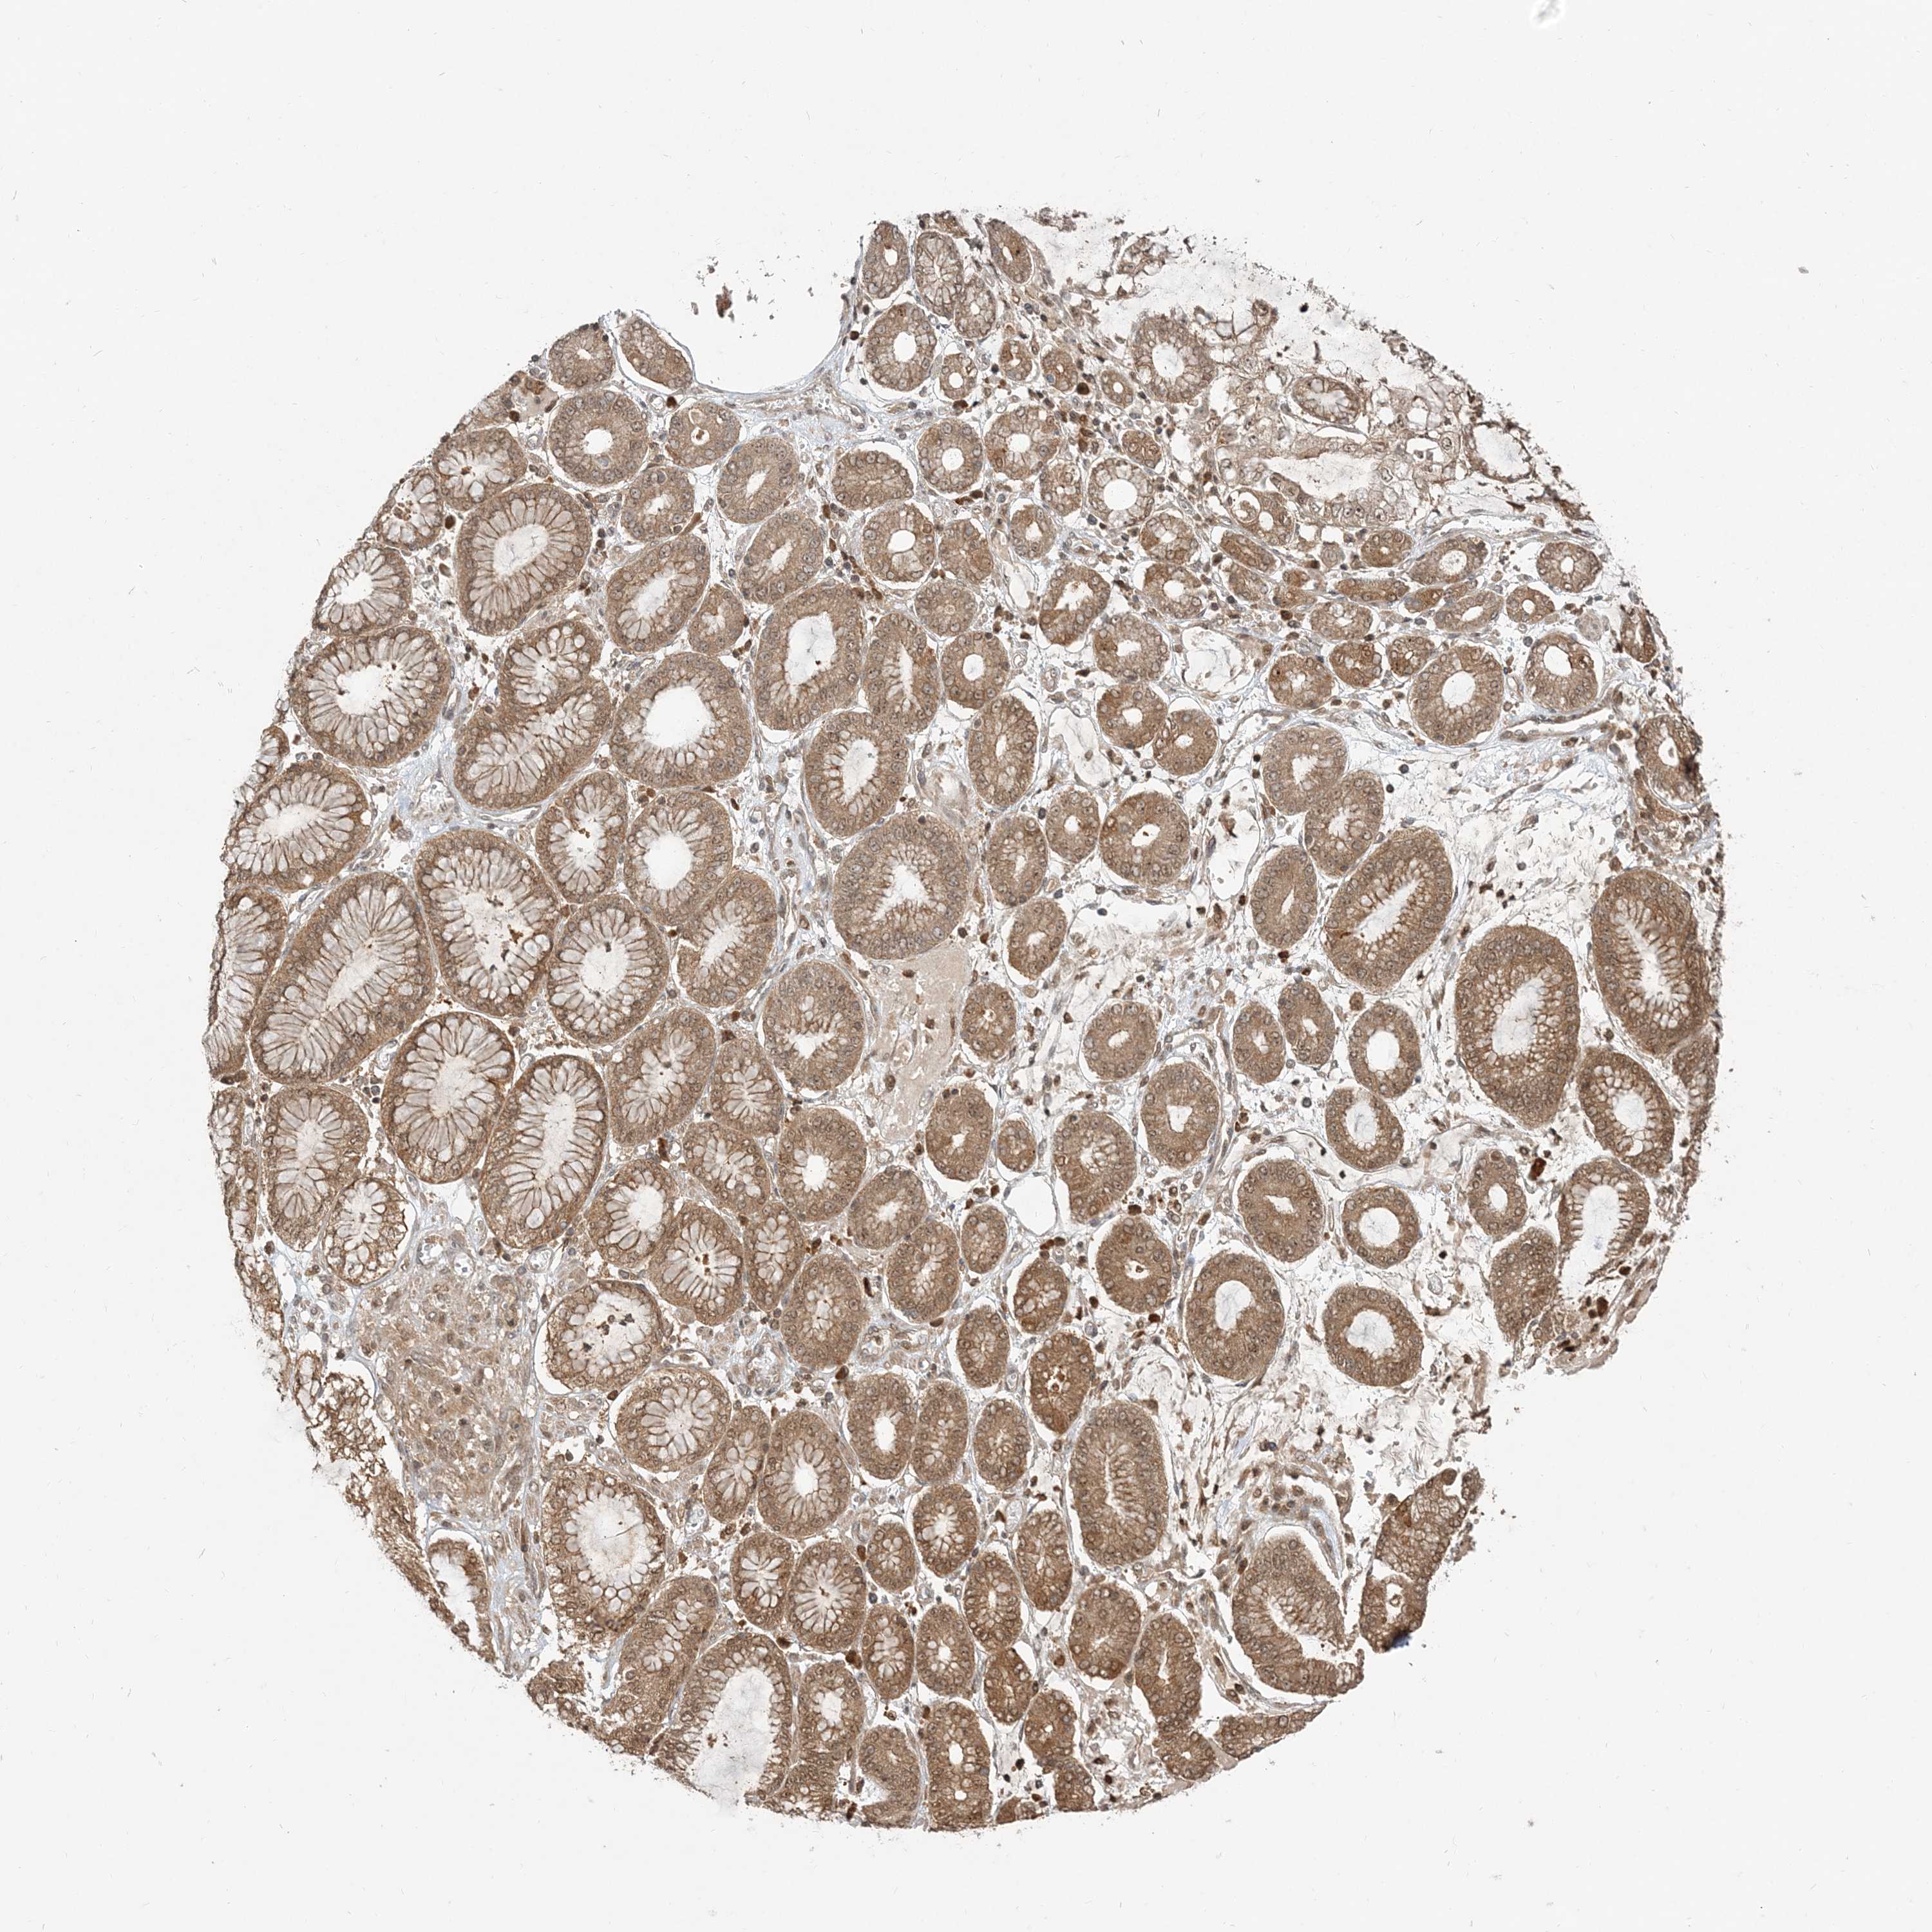

STOMACH CANCER - Protein expressioni

A mouse-over function shows sample information and annotation data. Click on an image to view it in a full screen mode. Samples can be filtered based on level of antibody staining by selecting one or several of the following categories: high, medium, low and not detected. The assay and annotation is described here.

Antibody stainingi

Antibody staining in the annotated cell types in the current human tissue is reported as not detected, low, medium, or high, based on conventional immunohistochemistry profiling in selected tissues. This score is based on the combination of the staining intensity and fraction of stained cells.

Each image is clickable and will lead to virtual microscopy that enables deeper exploration of all samples and also displays staining intensity scores, fraction scores and subcellular localization as well as patient and tissue information for each sample.

Antibody HPA076632

Antibody CAB037112

Staining

High

Medium

Low

Not detected

Intensity

Strong

Moderate

Weak

Negative

Quantity

>75%

75%-25%

<25%

None

Location

Nuclear

Cytoplasmic/membranous

Cytoplasmic/membranous,nuclear

Adenocarcinoma, NOS

Adenocarcinoma, High grade